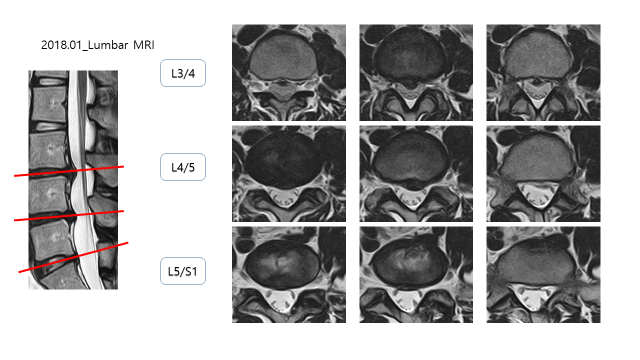

2018년도 MRI 상에서 디스크 탈출 소견이 있었음

L3/4 : DDD, Disc herniation

L4/5 : DDD, Disc protrusion

L5/S1 : bulging disc

이전에 촬영한 MRI와 비교를 하였을 때, 디스크 돌출/탈출 된 부분이 줄어든 것을 확인 할 수 있음.